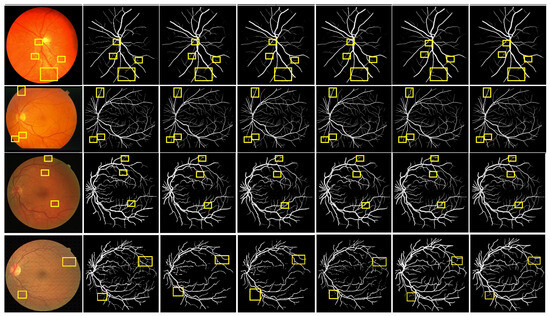

4.6. Qualitative Analysis

To verify the superiority of MPCCN, it was compared with different RVS algorithms, i.e., RVSA [46], ARDC-UNet [62], FAFFN [63], and TCU-NET [64]. The same experimental conditions and training strategies were used to perform RVS experiments on the DRIVE and CHASE_DB1 datasets. The experimental results are shown in Figure 8. From Figure 8 and Figure 9, it can be observed that RVSA [46], as a classic algorithm for RVS, can only segment the general direction and distribution of the vessels. However, it tends to show major vessel breaks and mis-segmentation at vessel intersections.

Building upon the foundation of RVSA [46], ARDC-UNet [62] replaces convolution blocks with residual convolutions. This allows for the fine extraction of the main vessel network without overfitting, thus outperforming the traditional U-Net. Nevertheless, TCU-NET [64] has a low accuracy rate for extracting tiny vessels and tends to produce false positive vessel areas. On the other hand, ARDC-UNet [62] introduces an attention gates mechanism at the skip connections, which helps to suppress noisy background regions while increasing the focus on vessel areas. This mechanism reduces the impact of background noise while extracting the main network, but mis-segmentation still occurs with tiny vessels.

Furthermore, FAFFN [63] introduced parallel channel and spatial attention modules at the bottom of U-Net, unifying local and global vessel information to achieve high-precision vessel segmentation. It can accurately segment both the main and tiny vessels, with high accuracy in tiny vessel segmentation. However, mis-segmentation still occurs at vessel edges. In contrast, the segmentation results of MPCCN are consistent with the manually segmented vessel images by experts. Compared to other algorithms, MPCCN maintains connectivity in tiny vessel segmentation, reduces the impact of background noise, and ensures vessel connectivity. Therefore, MPCCN finely preserves vessel structural information, has a certain degree of anti-interference capability, and achieves high-precision RVS.